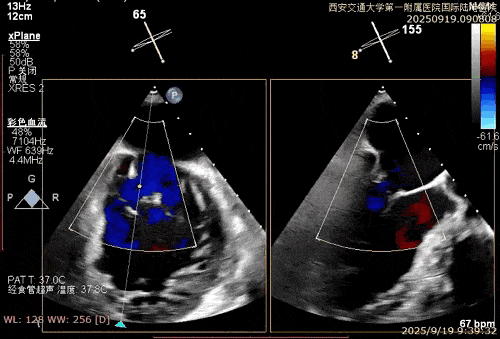

患者男性,69岁,术前TEE评估为FMR患者,因左室功能异常引发二尖瓣重度反流;后叶拴系,反流来源于整个2区,主要集中在2偏1、2偏3。患者瓣口面积约6.2cm²。房间隔可穿刺高度4.5cm。反流束宽度约19mm。AP径36.5mm。

术中在超声引导下完成房间隔穿刺,将第一枚XTR在左房内完成终定位,2偏3区完成植入,夹合效果良好,即刻超声显示轻微反流,完成夹子释放,手术效果良好,手术圆满结束,患者术后6小时即实现床旁活动。

经导管二尖瓣钳夹术作为近年来国际公认的微创治疗新技术,通过经血管介入路径,在食道超声与DSA影像引导下,利用特制钳夹将病变的二尖瓣叶边缘夹合,减少瓣口反流,从而改善心脏功能。